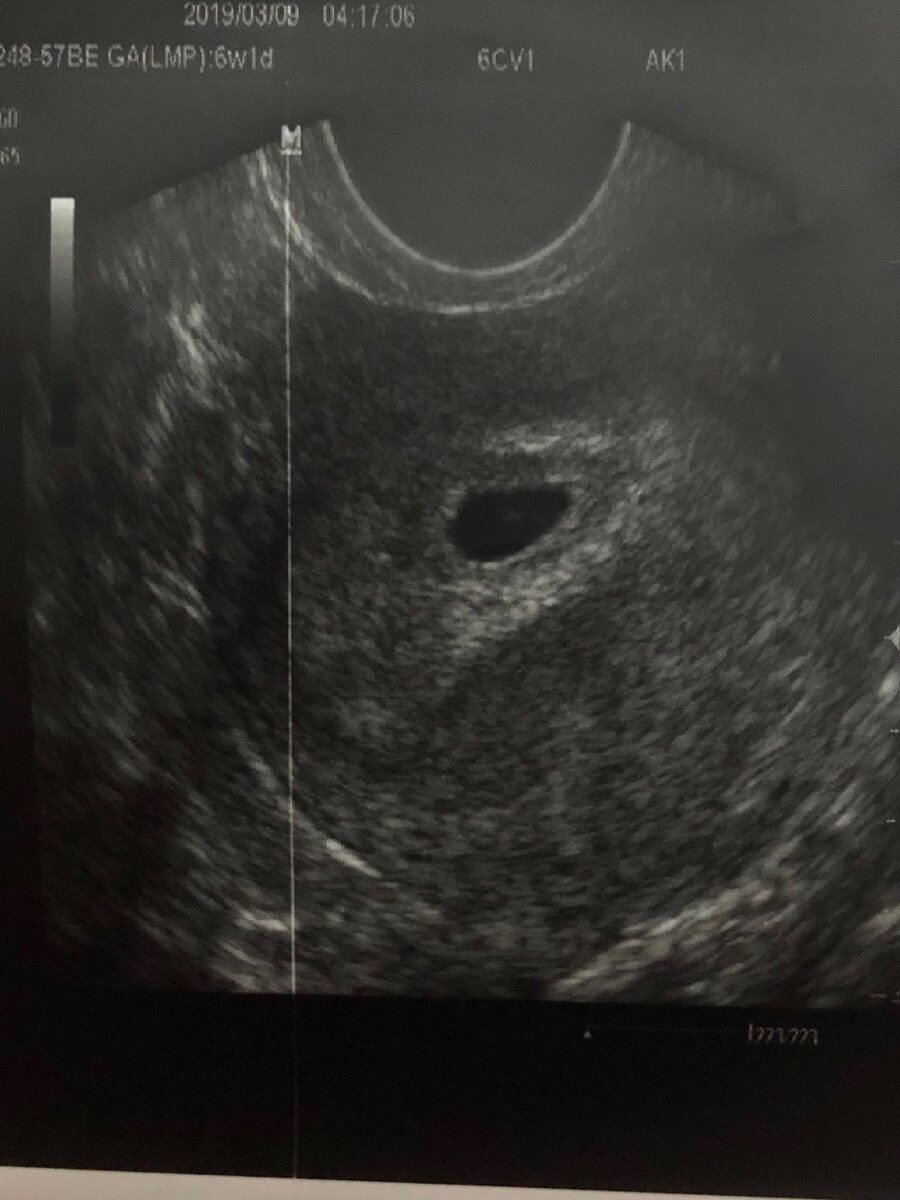

УЗИ на сроке 5 недель, видно пустое плодное яйцо без эмбриона

На раннем сроке УЗИ делают внутренним датчиком, такая себе процедурка, как будто не санкционированный половой акт. С результатом УЗИ возвращаюсь к своему врачу, она смотрит, говорит эмбрион не видно, пройдите УЗИ через две недели, возможно анэмбриония (пустое плодное яйцо).